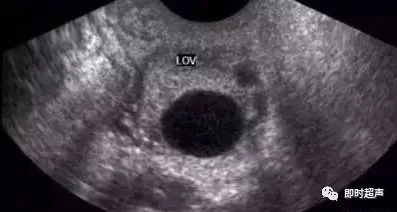

卵泡大小:优势卵泡直径达18-25mm为成熟标准;

形态与位置:饱满圆形、壁薄透声好,多位于卵巢表面;

排卵信号:卵泡消失或缩小、盆腔少量积液、卵巢内出现黄体回声。